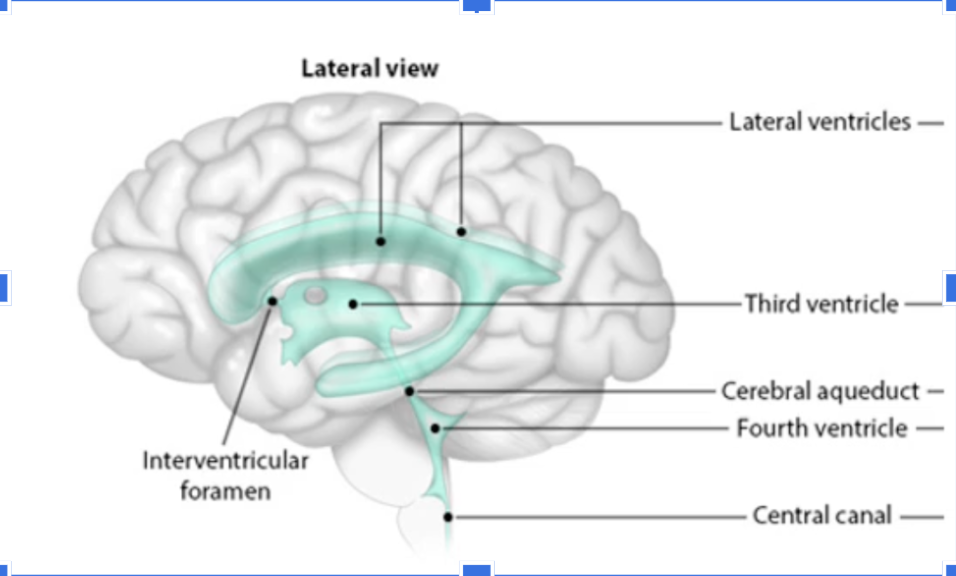

Trace CSF flow from Ventricles to Fourth Ventricle

Lateral Ventricles —> interventricular foramen—>Third Ventricle—> Cerebral aqueduct—>fourth ventricle

After leaving the Fourth Ventricle, where does the CSF go

It flows to the central canal or around the subarachnoid space to leave the brain